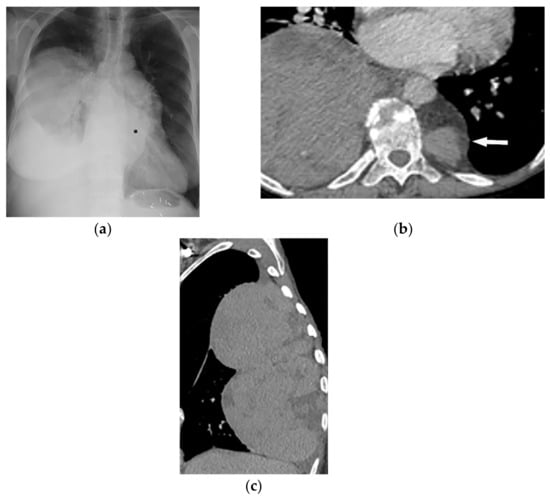

Its radiologic appearance varies from purely non-expansile osteolytic to multicystic mass with bony expansion. CT may reveal extrapleural mass with a well-circumscribed margin and “soap bubble” appearance in advanced cases (Figure 6a,b). MRI shows T1-hypointensity and T2-hyperintensity (Figure 6c) [16,25]. SBP tends to show metabolic activity on 18F-FDG PET/CT, which seems to be a risk of multiple myeloma transformation (Figure 6d,e) [26].

Figure 6.

A 63-year-old woman with incidentally detected mass at the left posteromedial chest wall. Axial chest CT with mediastinal (a) and bone (b) window show a well-defined expansile mass (arrow) with the destruction of the adjacent rib. There is no internal calcification. No neural foraminal extension was seen (not shown). (c) T2W images of another patient with the same pathology show mildly expansile marrow replacing lesions at proximal posterior rib with high T2 signal intensity without cortical disruption or soft tissue mass. Increased metabolic activity is present on 18F-FDG PET/CT (d) Axial and (e) sagittal (arrow).